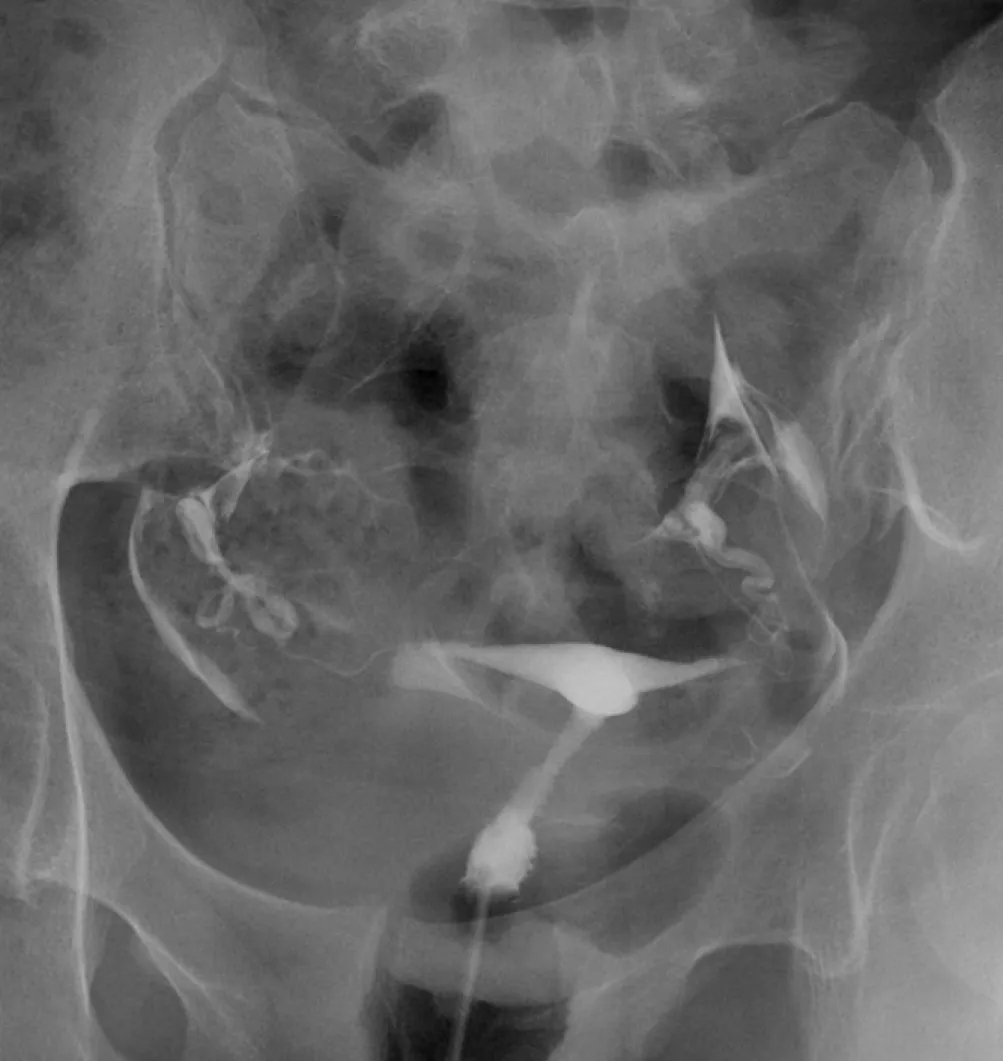

詳解

破題關鍵

這張子宮輸卵管攝影(HSG)顯示顯影劑從子宮頸進入子宮腔,再流經兩側輸卵管,最後從輸卵管末端溢出到骨盆腔,形成兩團模糊的顯影劑雲霧,這代表兩側輸卵管都是暢通的。

選項拆解

登入查看完整詳解與互動作答